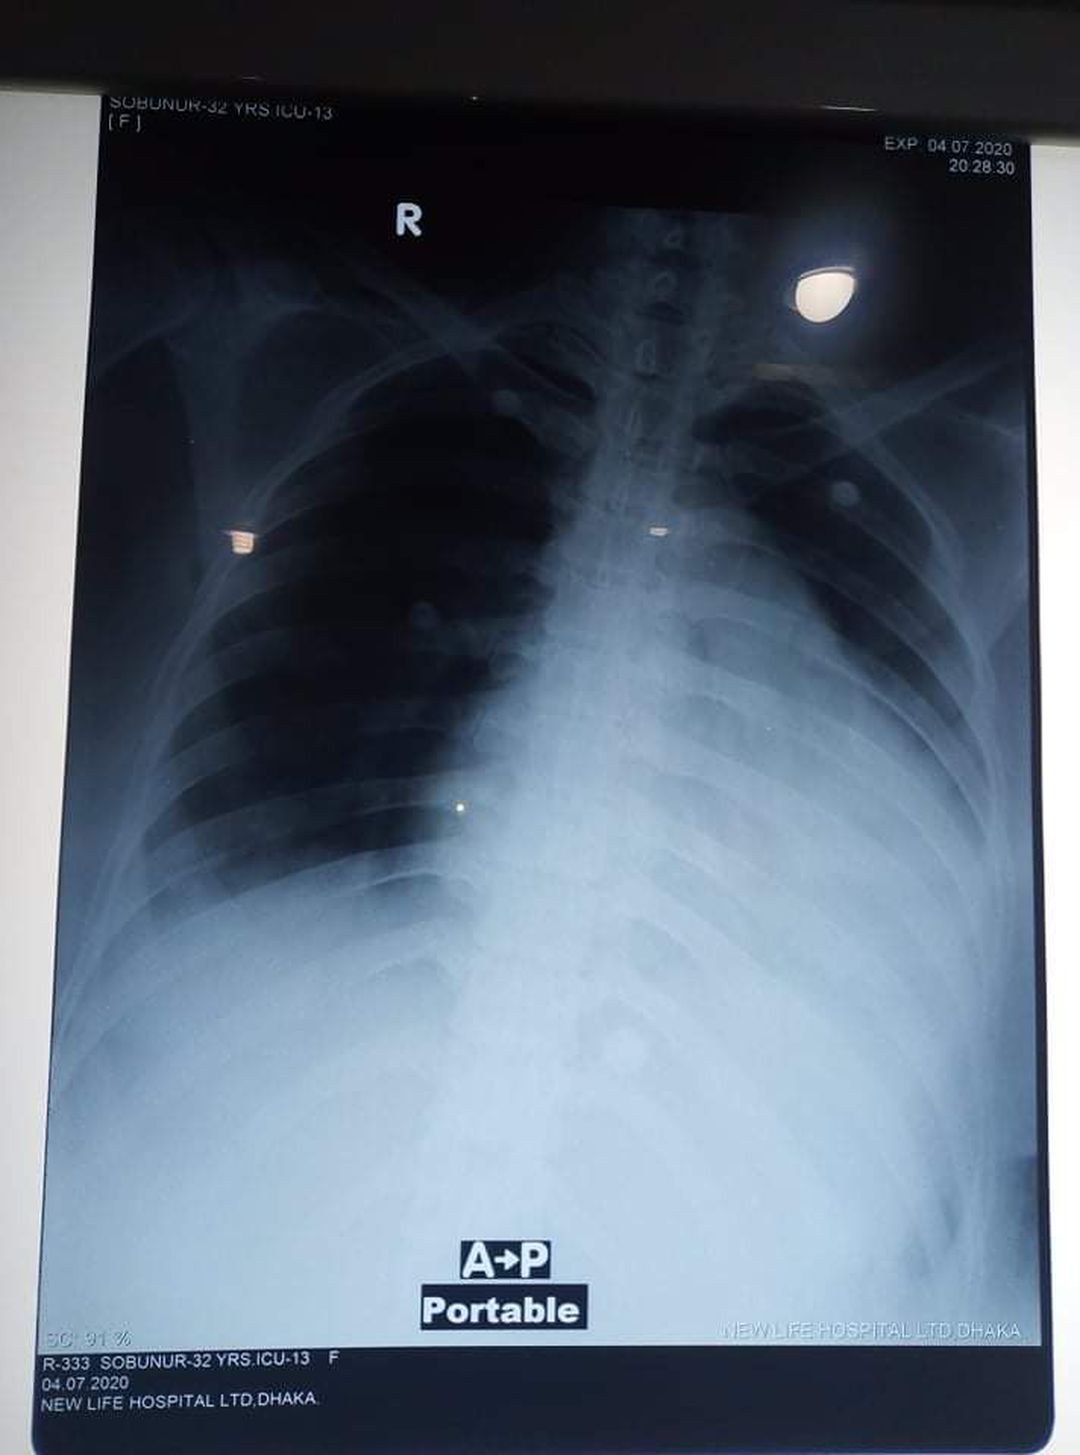

What is the diagnosis? Please explain in detail. It's very urgent

It has rotation please repeat it. History of patient?

Left ventricle heavily enlarged, maybe  heart failure or a heart valve disorder.